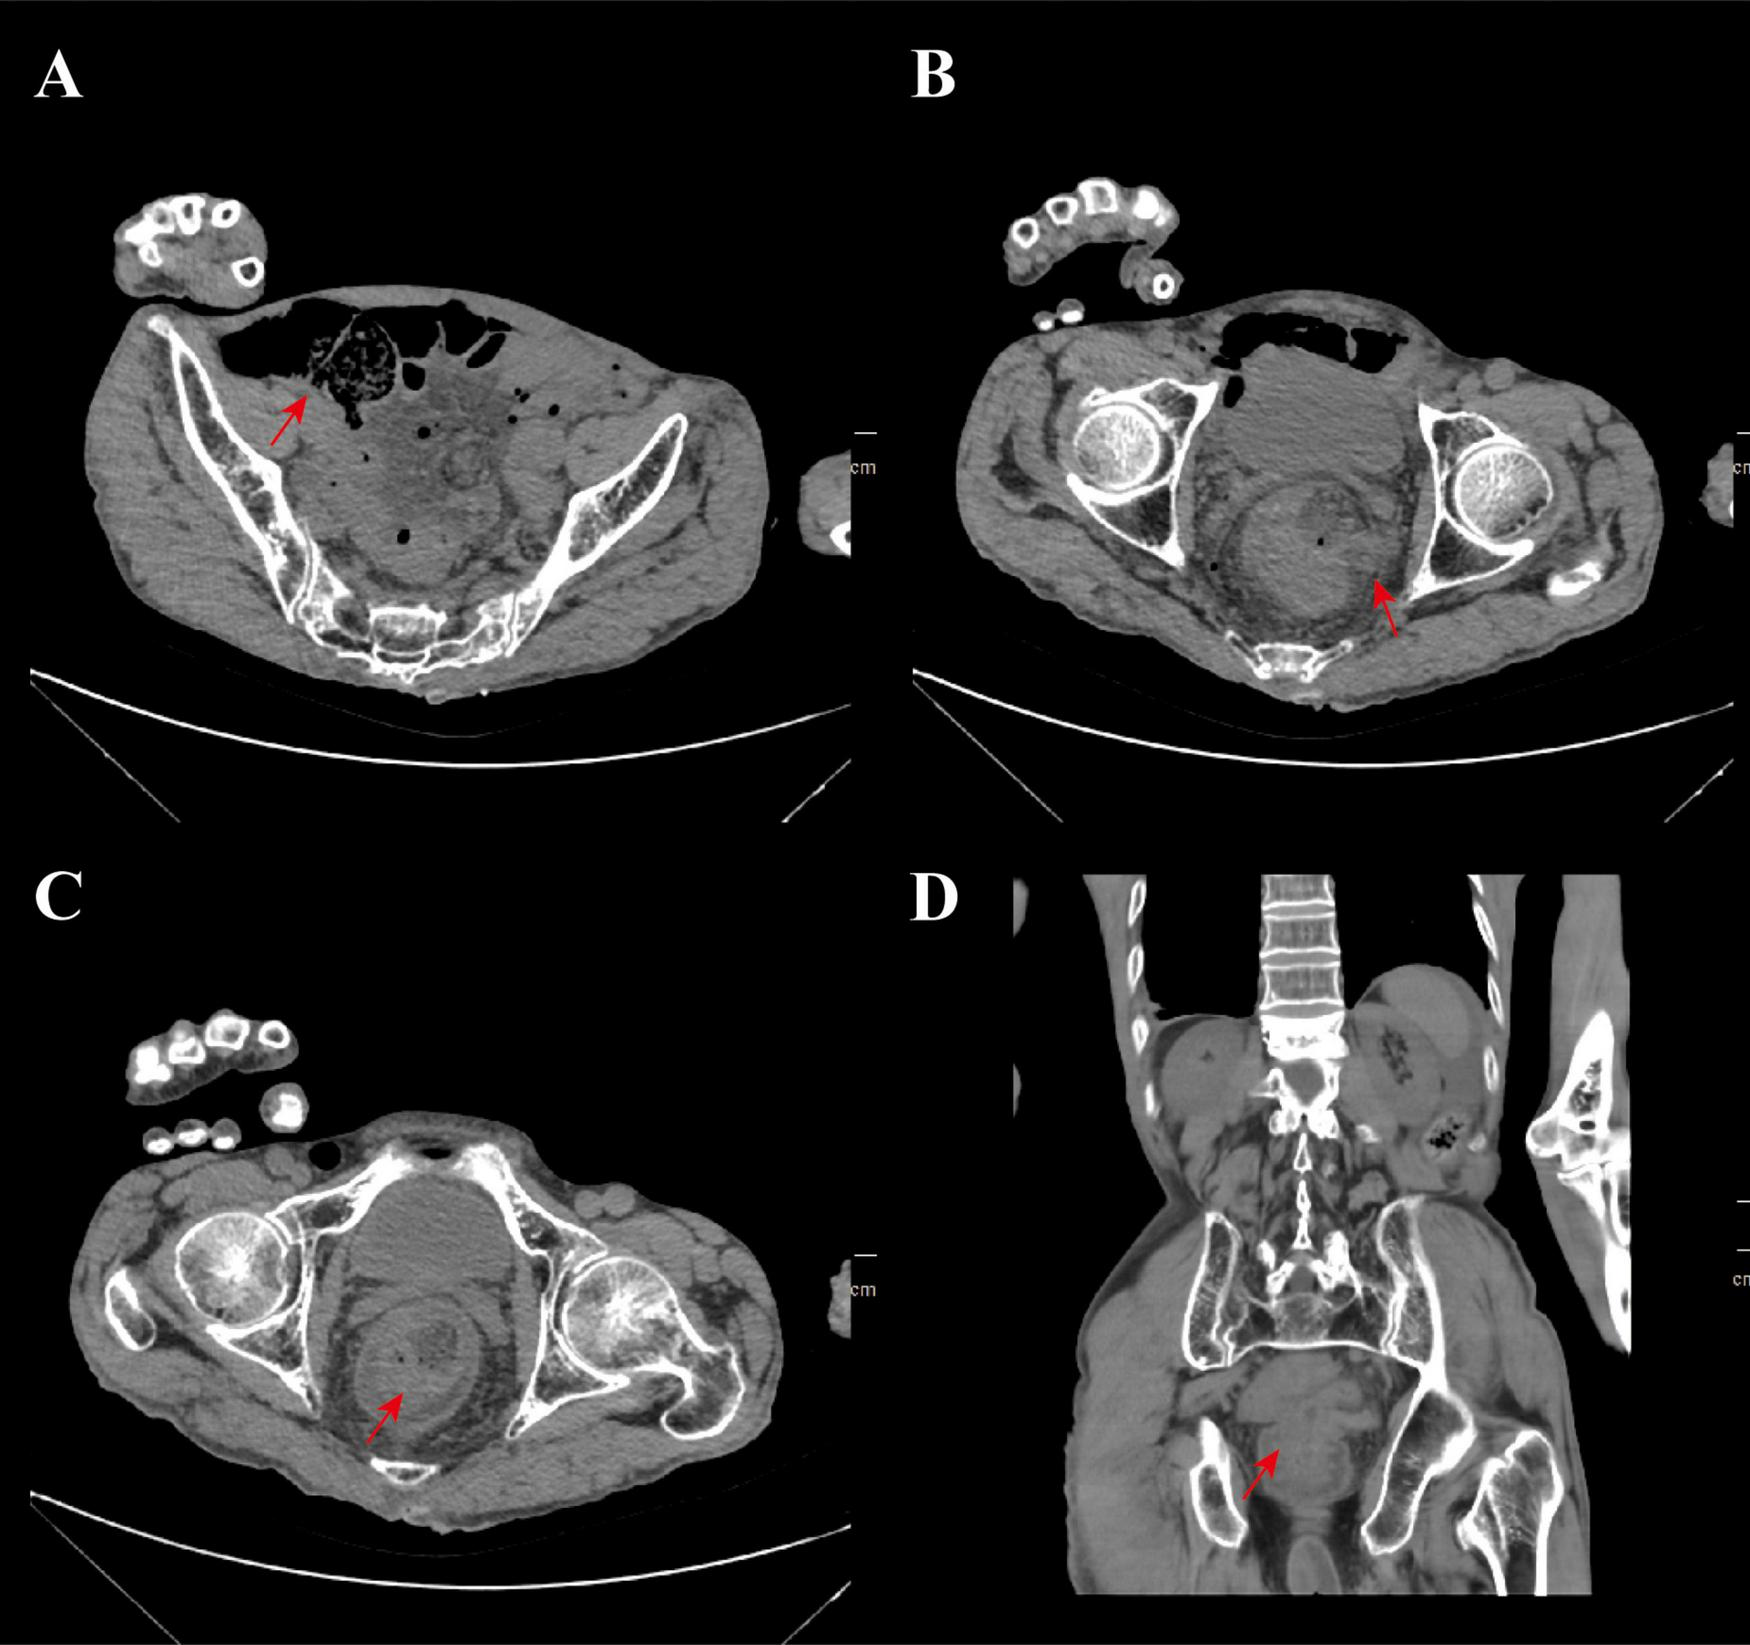

Due to rectal prolapse, the location of the rupture can be reached by digital rectal examination. We disinfected the small intestine with diluted iodophor solution and then sent it back into the abdominal cavity through the rupture. After returning the small intestine and rectum to their normal positions in the emergency department, imaging and laboratory tests were performed to assess the patient’s general condition. Computed tomography (CT) showed multiple free gas in the abdominal cavity, with the small intestine dilated and filled with gas (Figure 2A); diffuse exudation in the abdominal and pelvic cavities with multiple effusions; thickening of the intestinal wall in the lower segment of the rectum, with intestinal images visible inside, suggesting intussusception (Figures 2B, C); the lower end of the rectum protruded outside the anus, suggesting rectal prolapse (Figures 2C, D).

FIGURE 2

CT imaging findings. (A) The CT imaging manifestations of small intestine dilation and inflation, the red arrow indicates the dilation of the small intestine; (B) imaging manifestations of small intestine prolapse after rectal rupture and the red arrow indicates the site of rectal rupture; (C) the imaging shows that there is intussusception and rectal prolapse and the red arrow indicates the lesion site; (D) the coronal plane imaging manifestations of the patient, the red arrow indicates the location of recurrent rectal prolapse and intussusception.